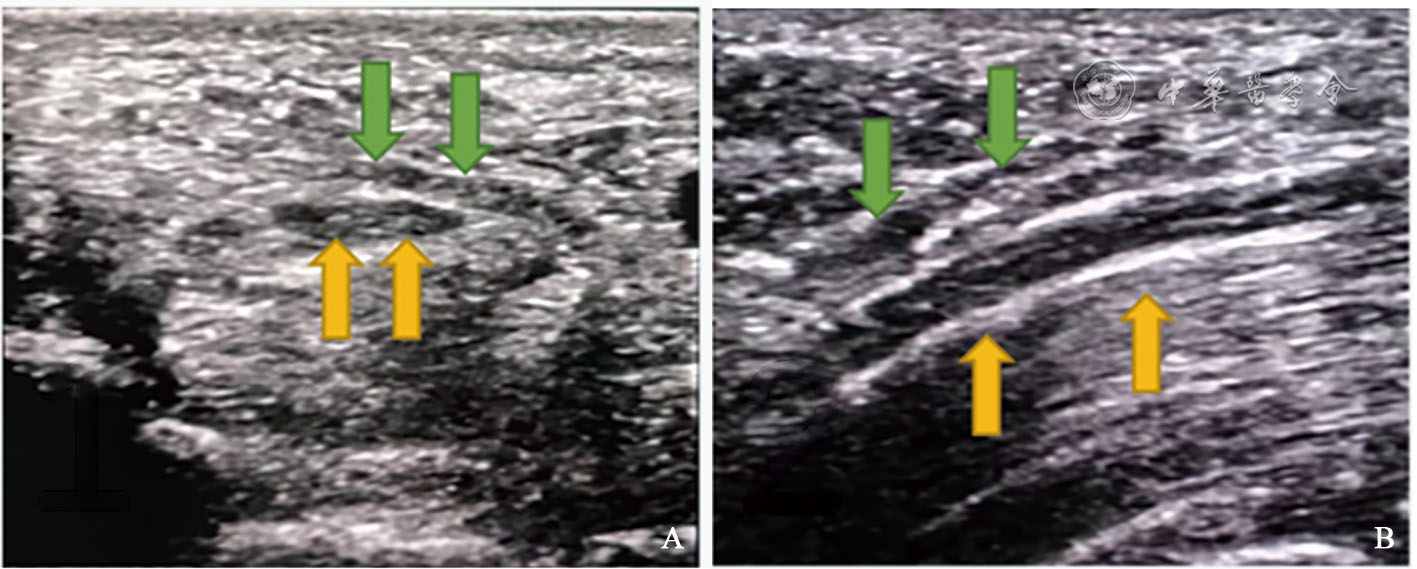

• 超声辅助定位经皮通道松解对慢性腕管综合征的临床疗效分析

探讨超声辅助定位经皮通道松解治疗慢性腕管综合征的临床疗效。

2020年11月至2023年12月,丹阳市人民医院手足外科收治符合入选标准的慢性腕管综合征患者66例,其中采用超声辅助定位经皮通道方法治疗的患者26例(超声组),采用掌根部纵行小切口治疗的患者40例(小切口组),均行腕管松解手术治疗,记录2组手术时间、切口长度及术后恢复等情况并进行对比。

超声辅助定位经皮通道松解治疗慢性腕管综合征,在减少组织破坏的同时精准切开增厚的腕横韧带,有效解除正中神经受压,具有手术切口位置准确、瘢痕短、早期柱状痛发生率低等优点,是一种可供选择的治疗腕管综合征的手术方式。